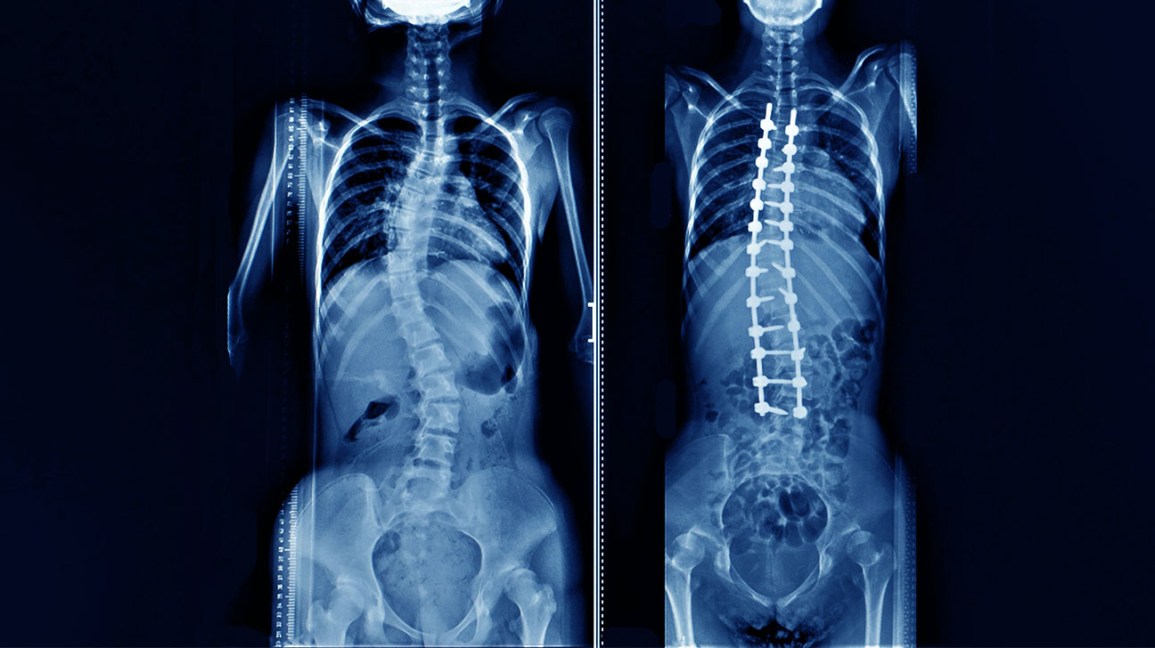

During surgery, your child's surgeon will use implants such as steel rods, hooks, screws, or other metal devices to straighten and stabilize your child's spine bones. Bone grafts are used to maintain the spine in place and prevent it from curving again.

A spinal fusion is used to treat scoliosis. The main concept is to straighten the bent vertebrae and fuse them together so that they recover into a single, solid bone. Scoliosis surgeons can drastically improve curves with the techniques and technologies available today.